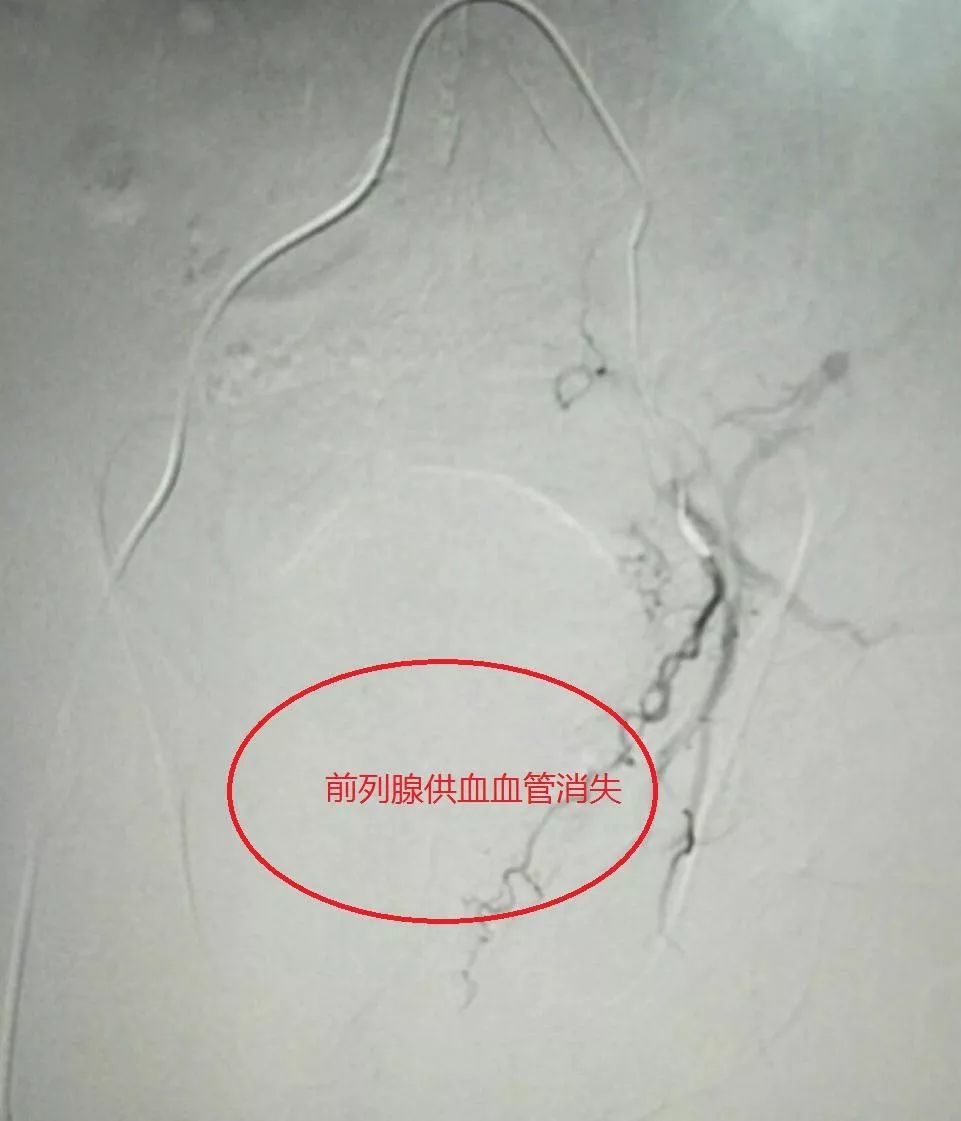

左侧前列腺供血血管栓塞后消失柳州市工人医院副院长,血管介入外科

图片尺寸961x1121